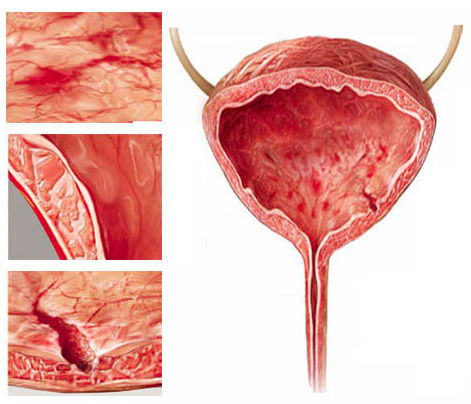

La uretromeatotomía es un procedimiento quirúrgico ambulatorio que se realiza para ampliar el meato uretral y el segmento distal de la uretra cuando existe una estrechez que dificulta la salida normal de la orina 🚻

Es una intervención frecuente en casos de estenosis del meato o estenosis uretral distal.

✔️ Chorro urinario fino o débil

✔️ Dificultad para iniciar la micción

✔️ Dolor o ardor al orinar

✔️ Desviación del chorro

✔️ Infecciones urinarias repetidas

Estos síntomas no deben normalizarse, ya que pueden progresar.